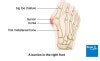

엄지발가락의 제1중족 족지 관절이 발의 외측으로 치는 변형입니다.

중족골은 내측으로, 근위 지골은 외측으로 전위되며, 제1중족 족지 관절의 점액낭에 염증이 발생하는 질환으로 회내 변형을 동반한 3차원적인 변형입니다.

처음에는 무지의 외반과, 제1중족골 내반뿐이지만 서서히 전족부의 횡아치가 무너져 개장족이 되며 소지내반증도 합병됩니다.

진행되면 무지는 제2족지 아래로도 파고들며, 제2족지는 망치 족지가 되고, 마지막에는 MTP관절이 병적 탈구됩니다.